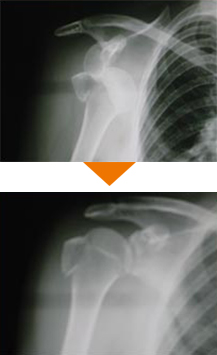

スポーツ外傷

スポーツ外傷、交通外傷、労働災害、家庭や職場による一般外傷などは認定医が適切な診断、診察を行います。